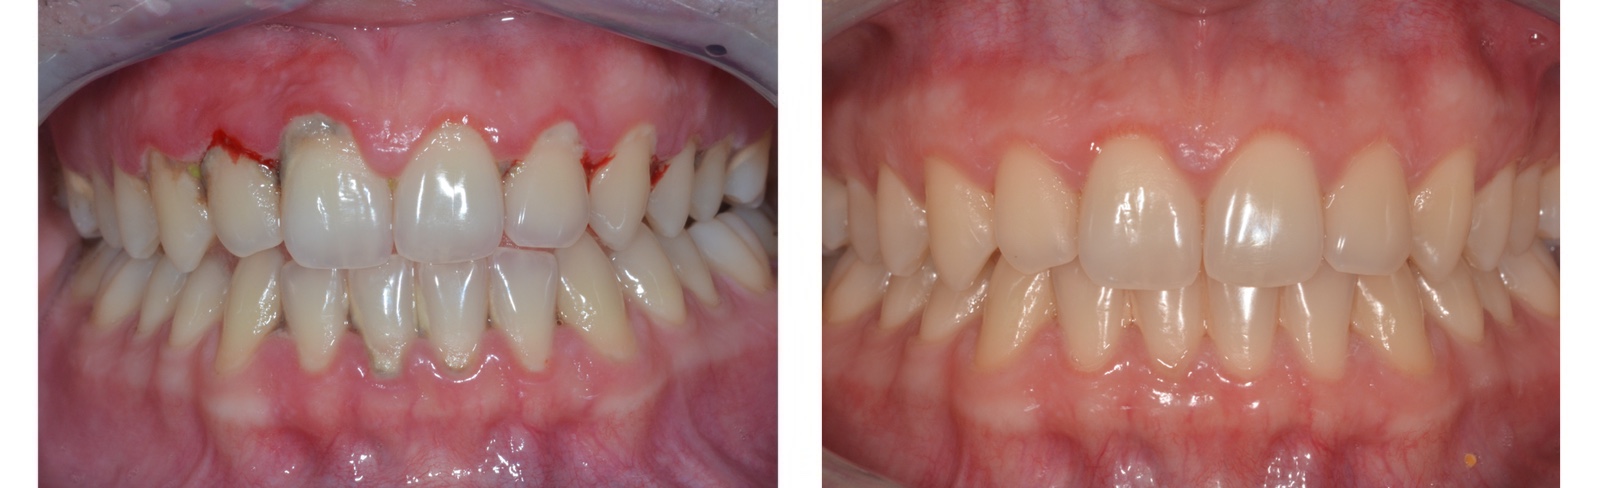

Krónikusan gyulladt, vérző íny kezelés előtt

Parodontális kezelést követő állapot